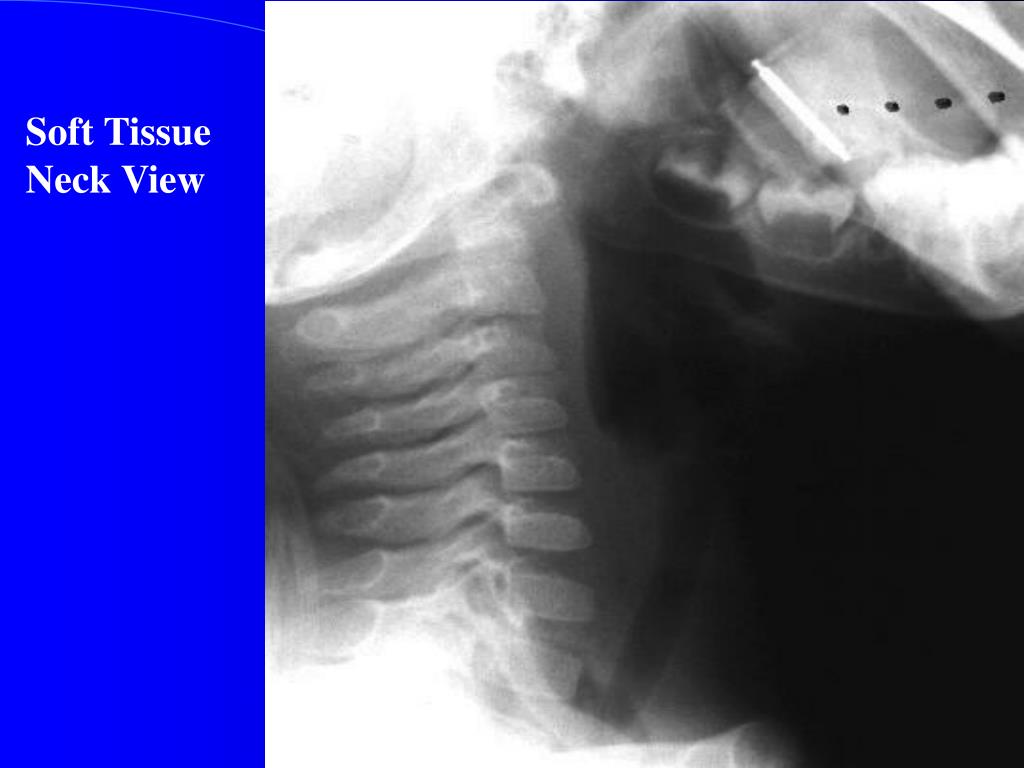

18. Soft tissue lateral neck radiograph

22. On Exam … Nasopharynx Bulging forward of the soft palate and nasal obstruction Oropharynx Bulging of posterior phyaryngeal wall or Not visualized Soft Tissue Neck Film Patient position – MILD EXTENSION Positive Film - Retropharyngeal soft tissue > ½ the width of the adjacent vertebral body - may see air in the retropharynx

27. Soft Tissue Neck View